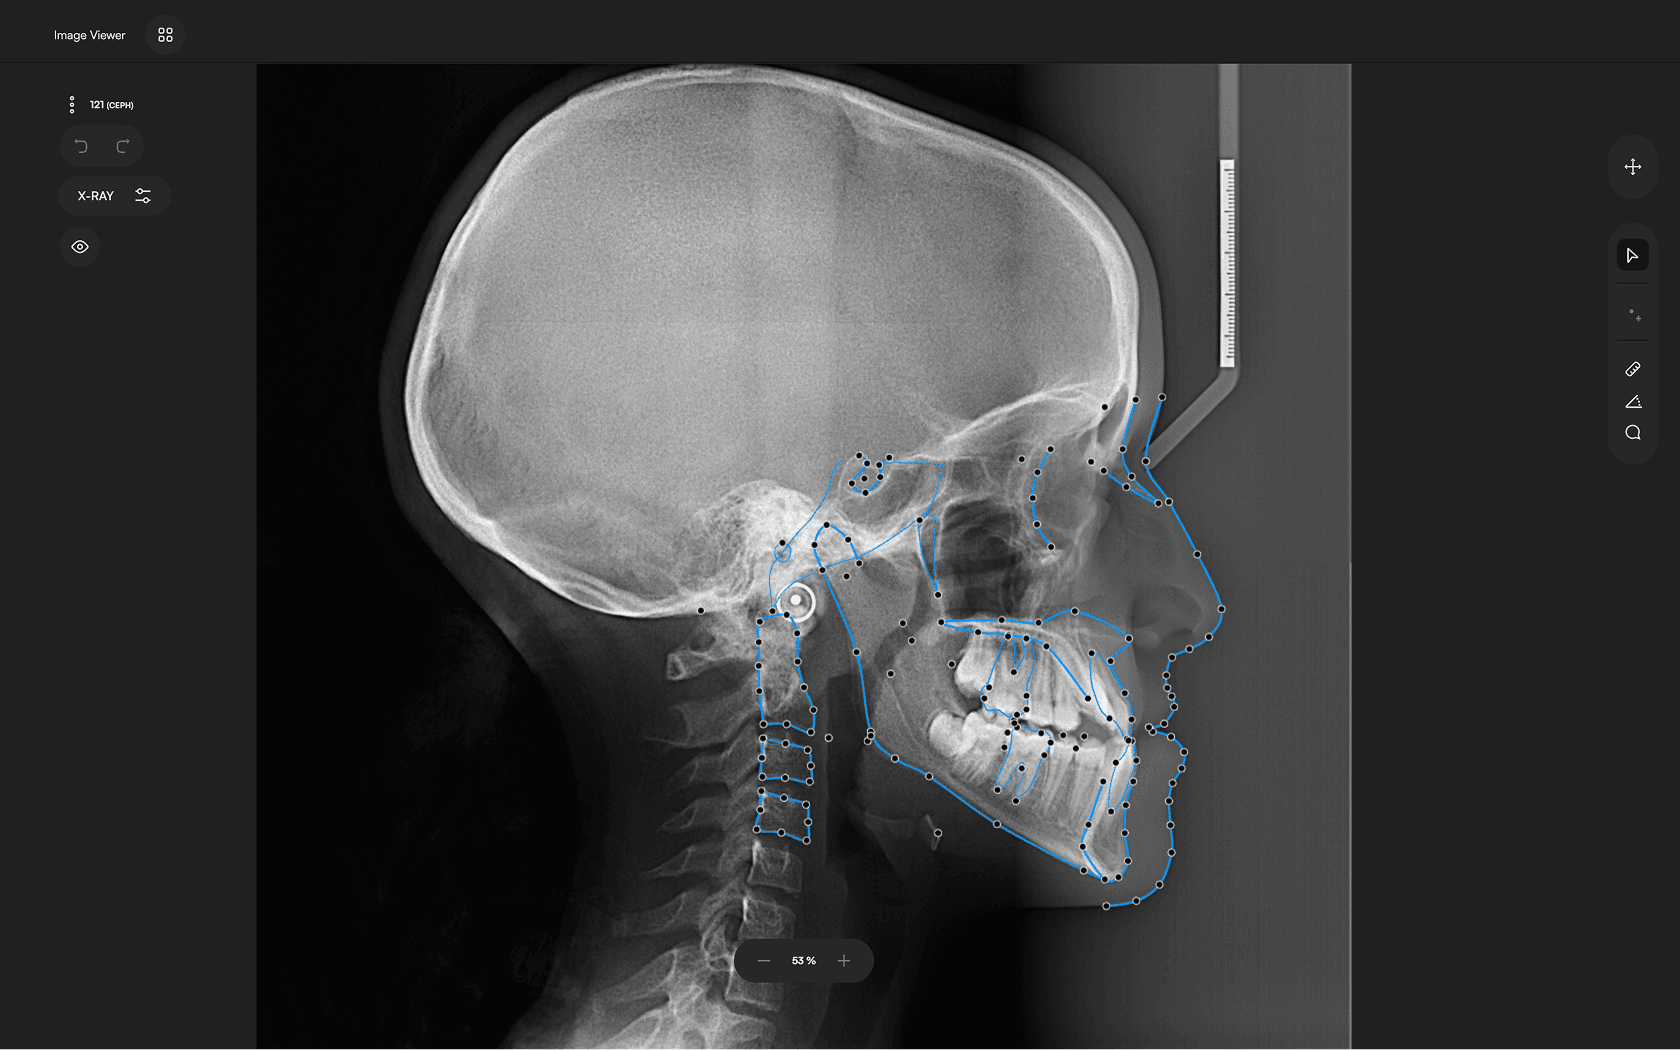

150+ landmarks traced in seconds

Identify 150+ orthodontic landmarks in under 10 seconds — a task that

traditionally may take more than 30 minutes.